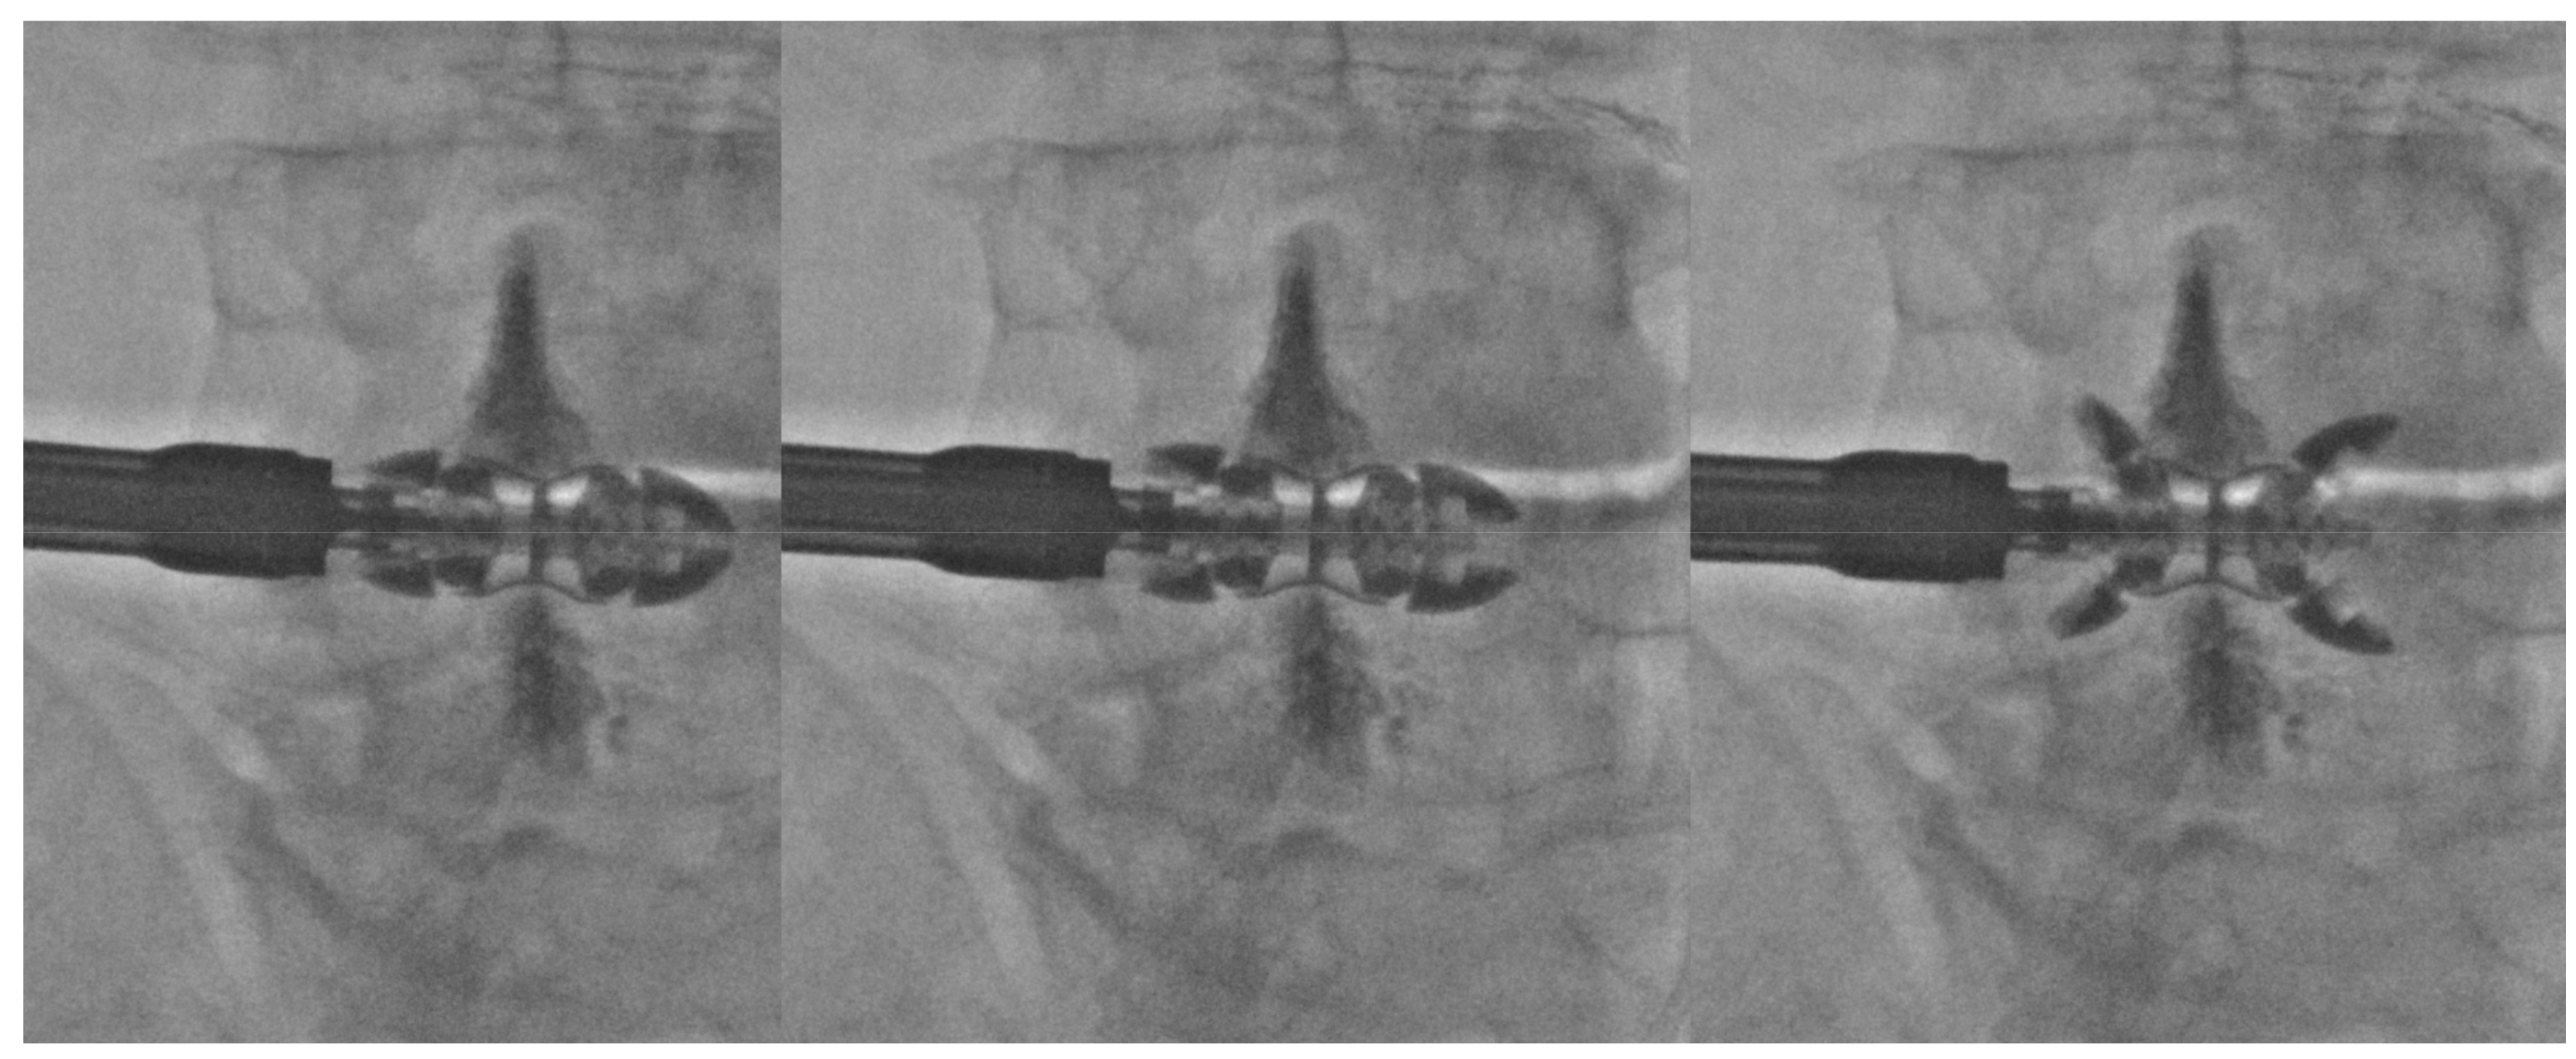

- Manfré, L. Posterior Arch Augmentation (Spinoplasty) before and after Single and Double Interspinous Spacer Introduction at the Same Level: Preventing and Treating the Failure? Interv Neuroradiol. 2014, 20, 626–631. [Google Scholar] [CrossRef]